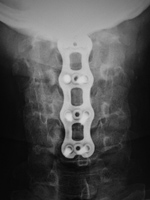

Cervical spine anterior and posterior fusion Cervical spine anterior and posterior fusion with intervertebral bone struts (plugs)

Anterior and posterior cervical spine fusion AP view Anterior and posterior cervical spine fusion lateral view Anterior and cervical spine fusion with intervertebral bone struts Anterior and cervical spine fusion with intervertebral bone struts

Young woman with traumatic locked facets at C6-7 and C7 body fracture. A posterior cervical fusion with lateral mass screws (cervical spine) and pedicle screws (thoracic spine) and rods extends from C4 to T2. There is an anterior cervical fusion plate and screws at C6-7 with a intervertebral disk cage at C6-7 and a crosslink at C6. There is an anterior cervical fusion plate that extends from C3 to C7 and posterior lateral mass screws and rods on each side from C3 to C7. Intervertebral bone struts (plugs) are present at the disk spaces from C3 to C6.